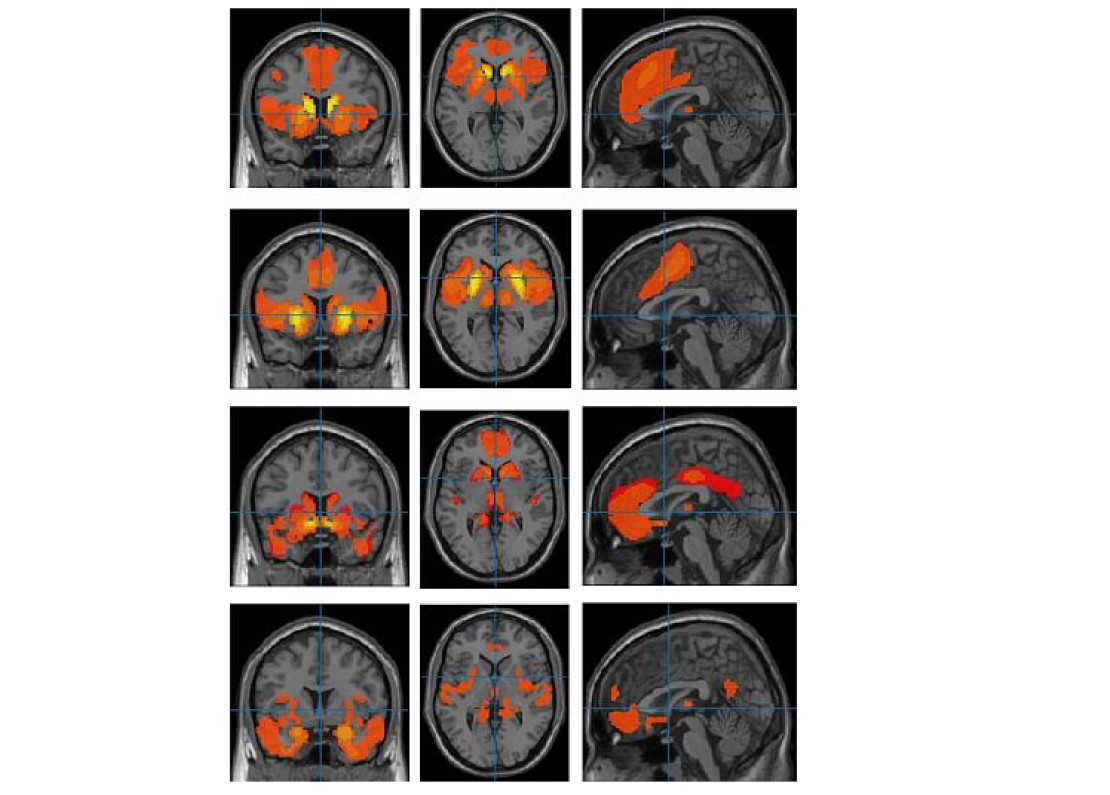

Frontiers in Psychiatry📷Области максимальной мозговой активности при воспоминании эмоций (сверху вниз): грусть — правая височная кора, радость — орбитофронтальная кора, страх — лимбическая система

Другой подход применили нейропсихологи из Миланского университета Бикокка. Здесь участникам показывали эмоциональные сценки — радостные, пугающие или грустные — и просили вспомнить и пережить соответствующее чувство, затем мозговая активность регистрировалась с помощью ЭЭГ.

При грусти активизировалась правая височная кора, при страхе — лимбическая система, включая амигдалу — область мозга, отвечающую за распознавание угроз и запуск реакций страха. Радость сопровождалась яркой работой затылочных областей и орбитофронтальной коры, которая связана с системой вознаграждения. Эти различия в активации доказывают: даже при воспоминании эмоций мозг формирует устойчивые и различимые нейронные паттерны, которые можно использовать для создания нейроинтерфейсов — например, для общения с людьми, неспособными говорить.